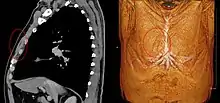

Musculus sternalis seen at axial CT and volume rendering.